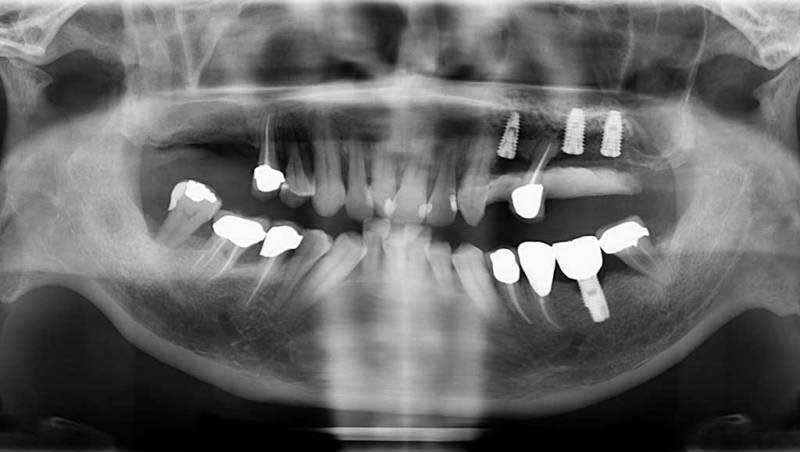

鼻竇增高術術前